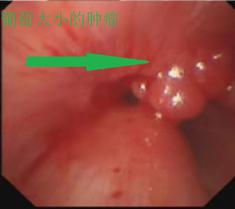

胸部CT及之后支气管镜检查证实了气管内塞满了一粒粒葡萄大小的肿瘤。而且肿瘤向下长到气管胸骨入口以下,即使行气管插管也没有用,如果不积极处理,患者会被活活憋死。